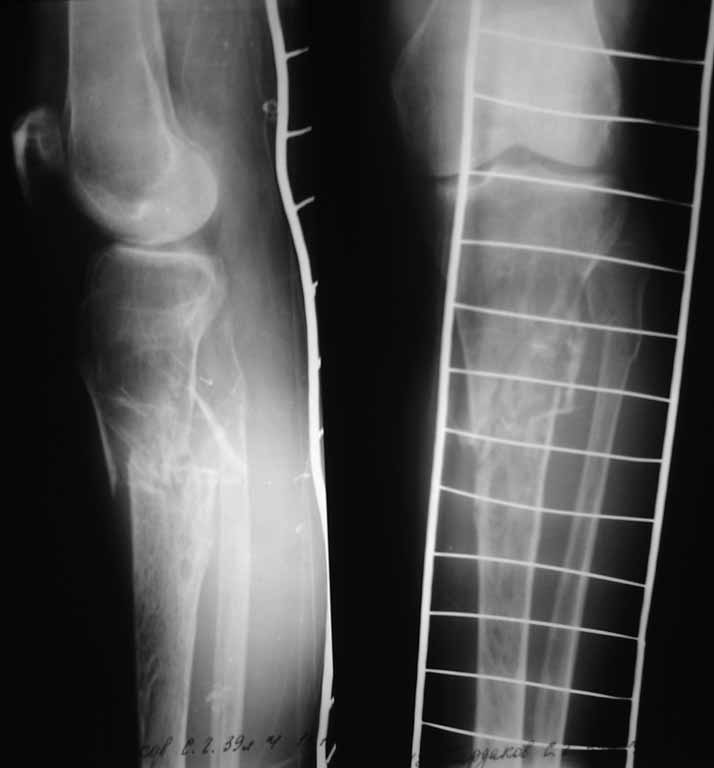

Диагноз:Закрытый, неосложненный, оскольчатый перелом проксимального метаэпифиза большеберцовой кости, верхней трети малоберцовой кости левой голени со смещением. Снимки прилагаются. Как вы считаете, какая тактика будет более рациональна у данного больного, учитывая его сопутствующий диагноз?